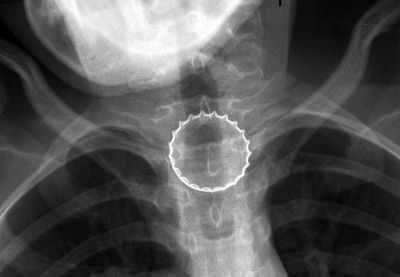

נערה עם צרכים מיוחדים, הגיעה לבית החולים בנהריה, כשהיא סובלת מכאבי גרון, לאחר בדיקות, התברר שבלעה פקק של בירת קורונה, שהוצא באמצעות ציוד אנדוסקופי (בריאות)